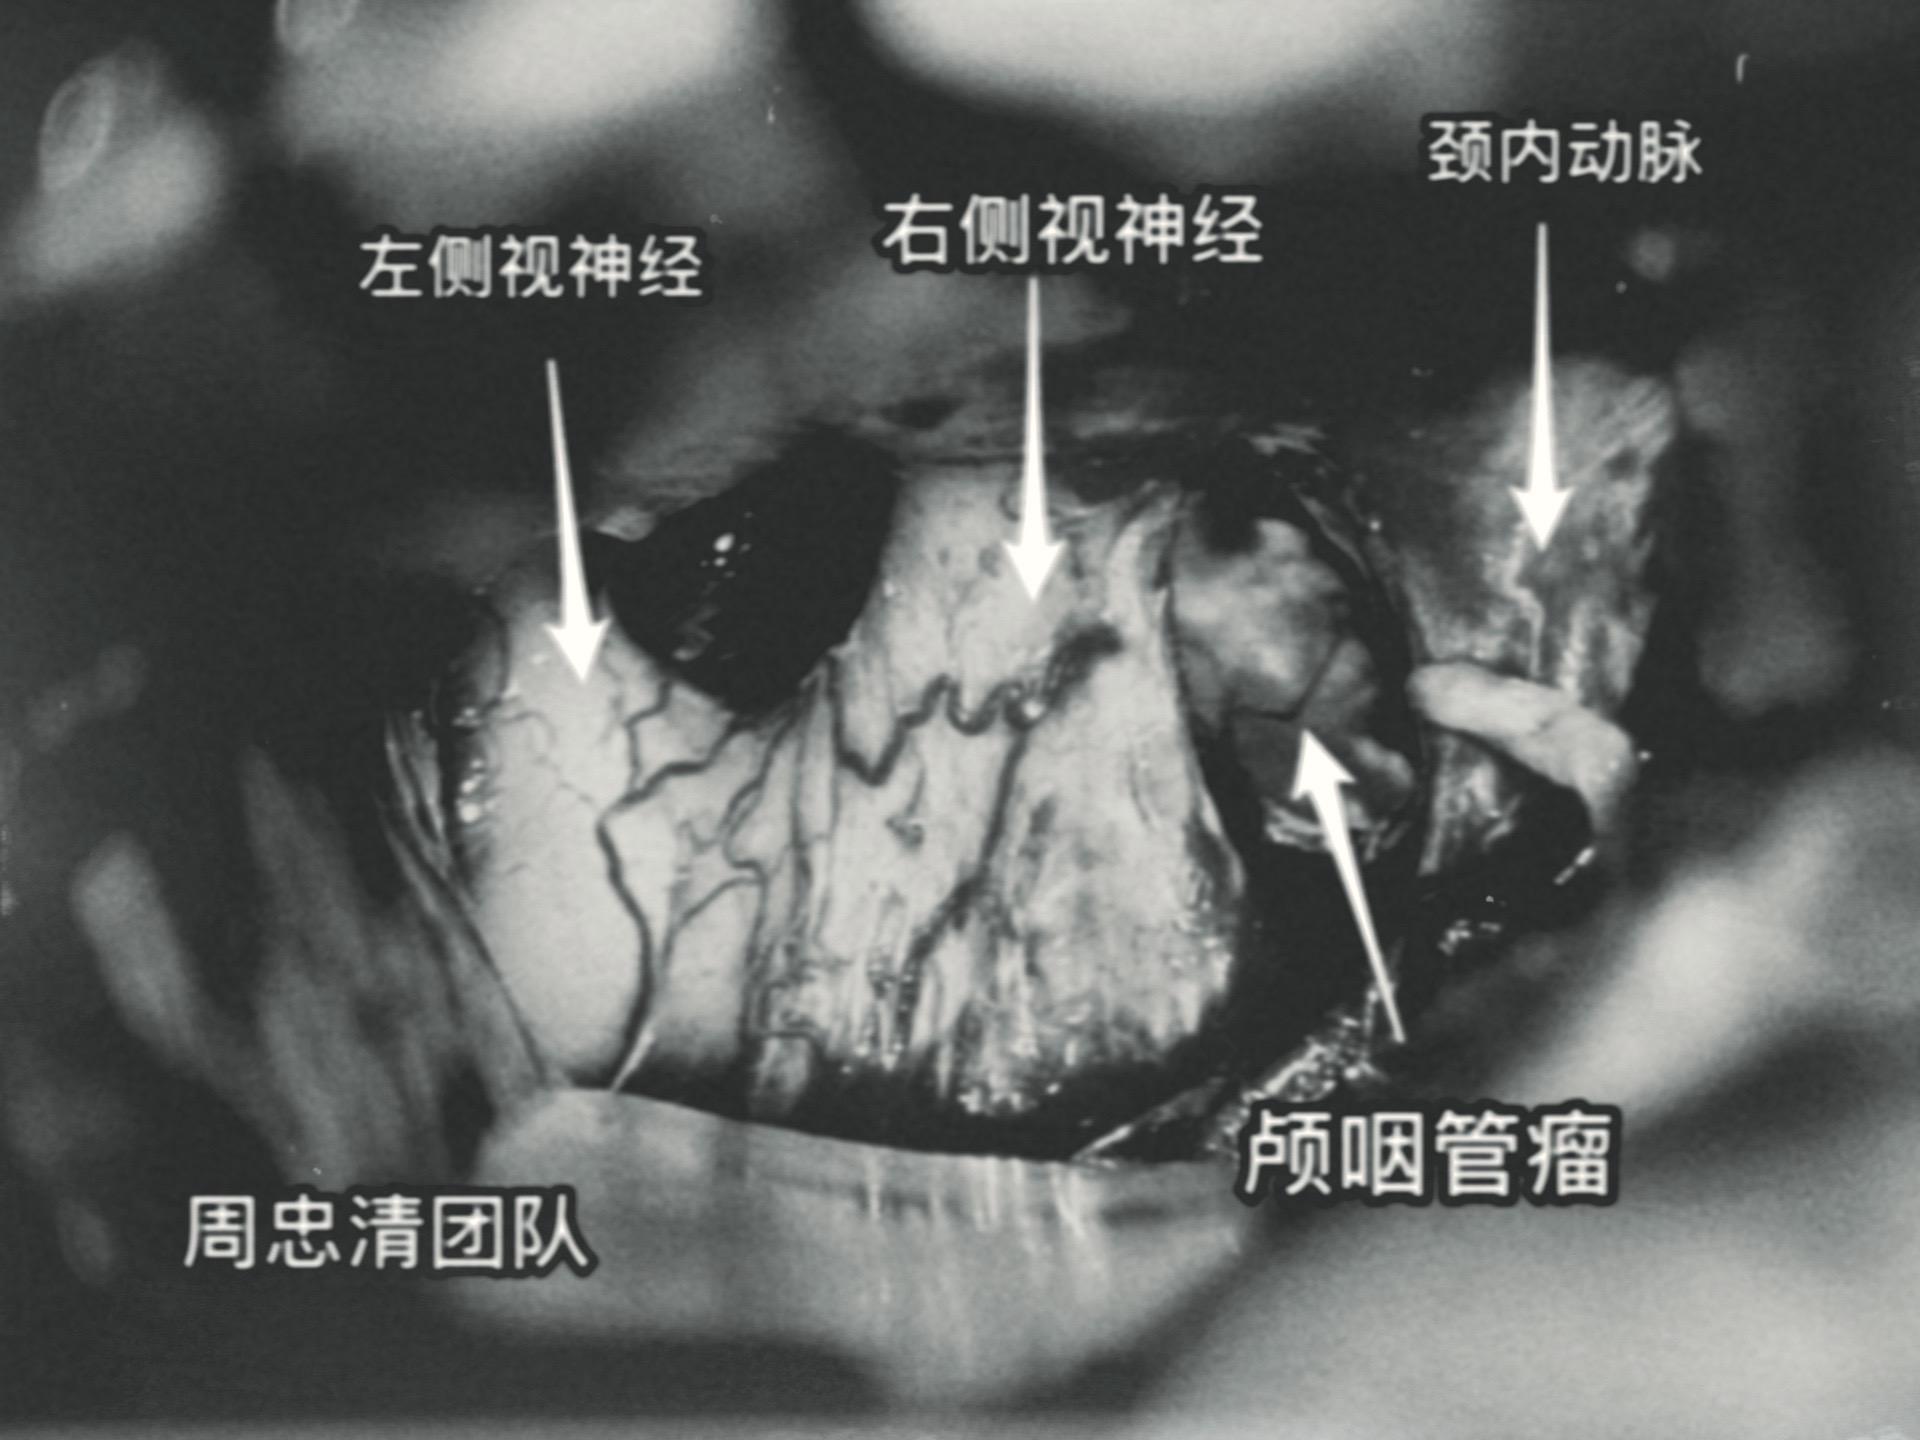

百日咳导致患儿颅咽管瘤手术推迟了三个月。7岁 男孩子三个月前因颅咽管瘤复发,住院准备作颅咽管瘤切除手术。 谁知意外事件不期而遇。 患儿咳嗽不止,只好出院到儿童医院治疗,经检测,咳嗽的原因是百日咳,经过治疗,咳嗽的问题彻底治愈了,过了三个月再次回到三博脑科医院。 2024年6月11日作了开颅手术。颅咽管瘤体积虽然不算大,其实不是一个肿瘤,而是四个肿瘤挨在一起了。 肿瘤当然是完全切除了。好事多磨!颅咽管瘤百日咳